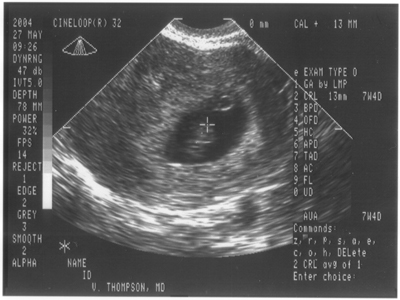

27. Mai 2004